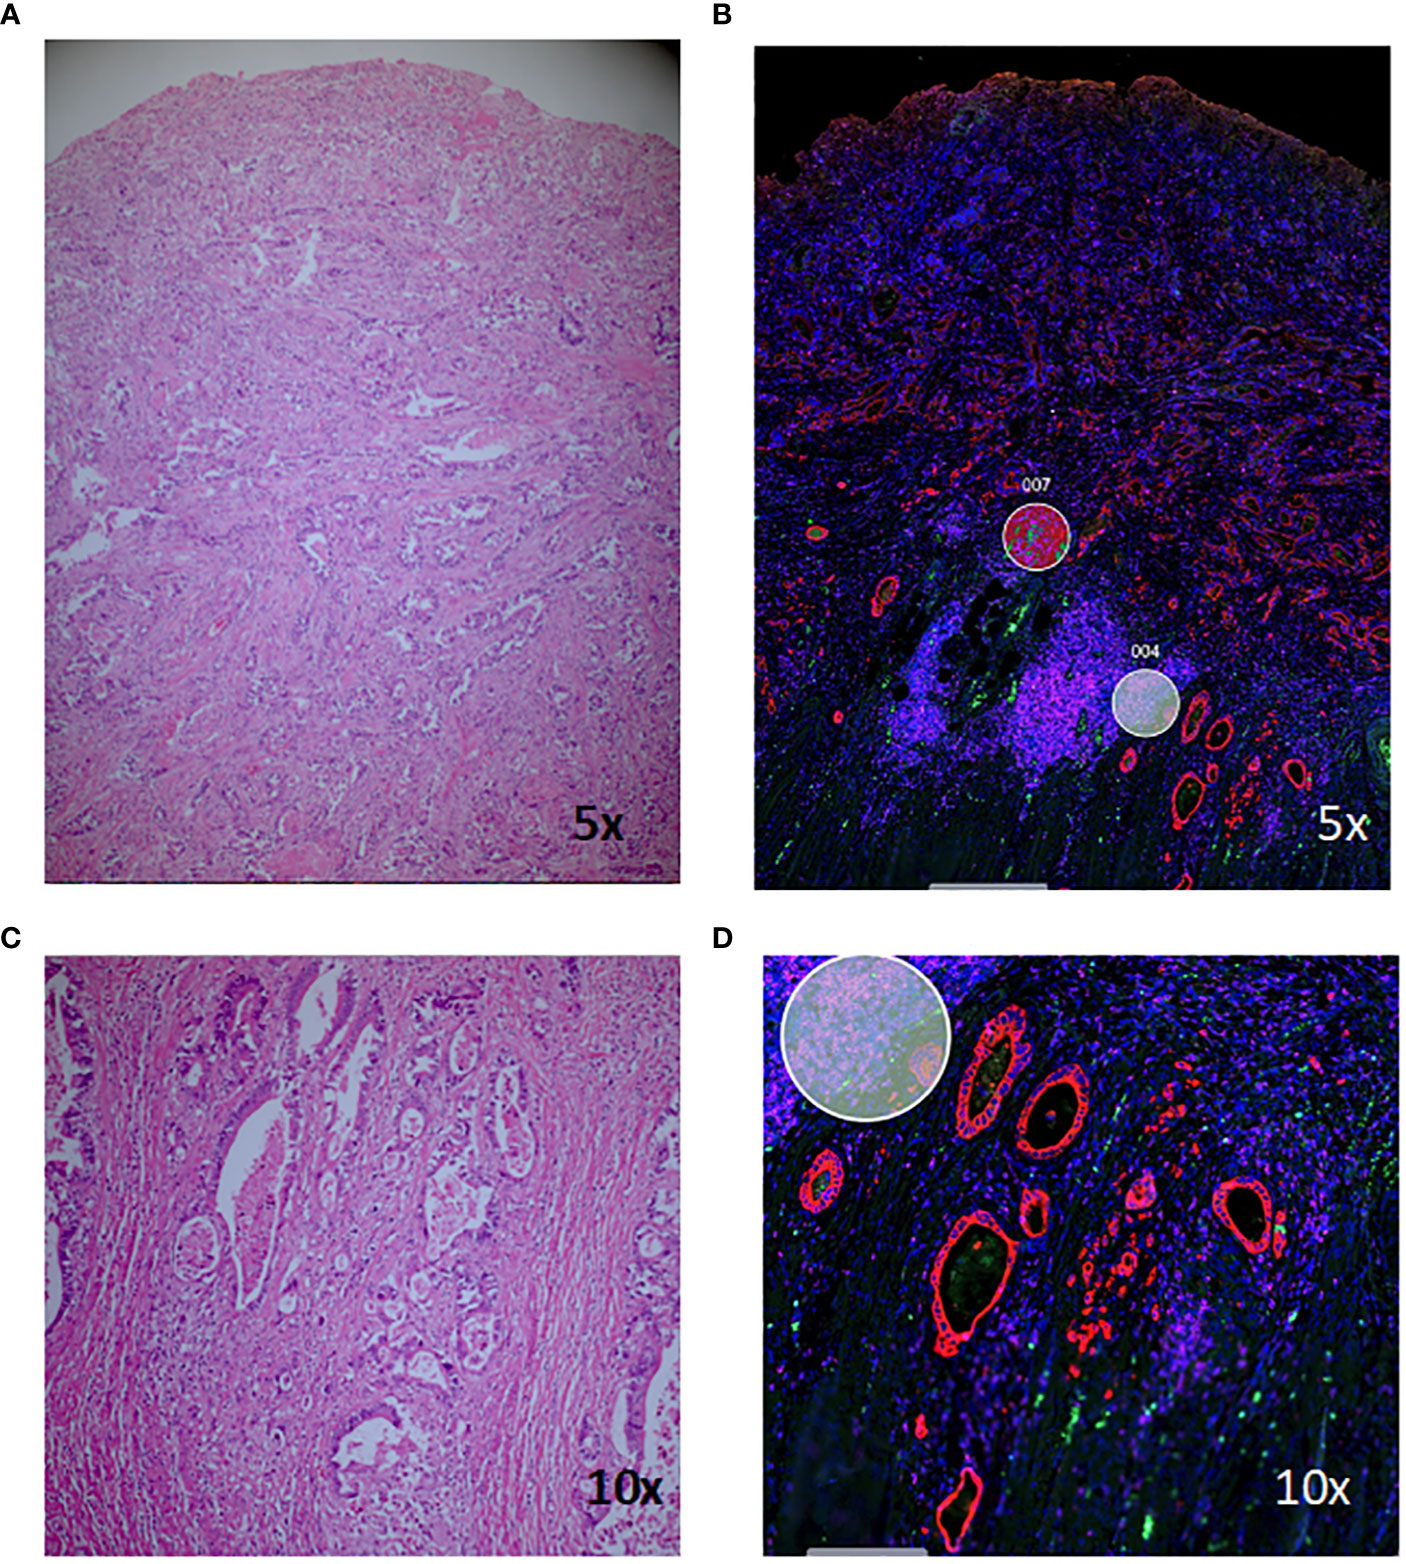

New technology uncovers complexities of colitis-associated colorectal cancer

Digital spatial profiling (DSP) tissue analysis is shedding new light on the molecular changes in colitis-associated colorectal cancer and signalling early biomarkers to identify t

Illuminating tumour micro environments

Advanced technical imaging capabilities and research projects supported by MWC are helping to identify new prognostic and diagnostic biomarkers to advance potential therapeutic tar